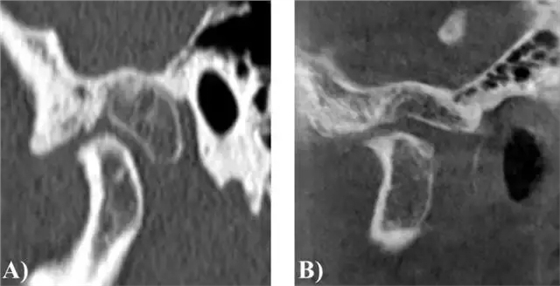

圖 1. 病例 1 的 CT 圖像 (A)術(shù)前 (B)術(shù)后

術(shù)后愈合良好,無明顯并發(fā)癥。病理診斷不太明確,但指出具有骨軟骨瘤的特點。術(shù)后 4 年采用視覺模擬評分法檢查病人,無疼痛(0 分)和無功能障礙(0 分)。

最大開口度為 45mm,左側(cè)錯合畸形得到明顯改善,術(shù)后 15 個月影像學(xué)檢查見髁突位于關(guān)節(jié)窩中央,髁突前方見一小骨贅。